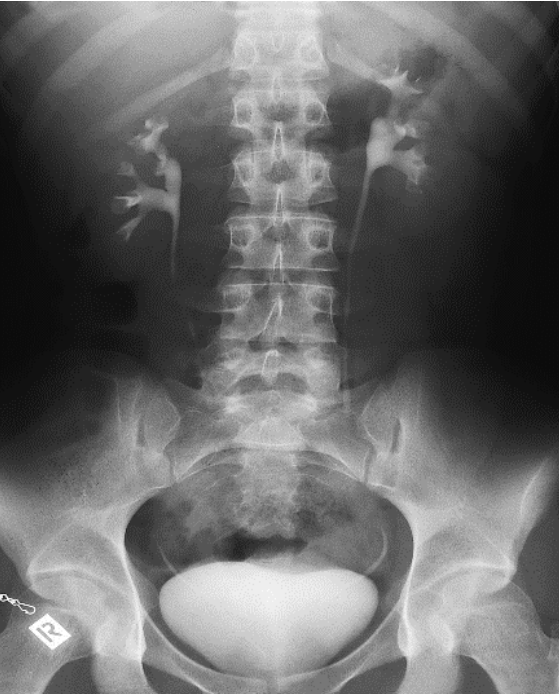

Które badanie zostało zarejestrowane na przedstawionym radiogramie?

Ilustracja do pytania 21

A. Jamy brzusznej wykonane poziomą wiązką promieniowania.

B. Płuc wykonane metodą Przybylskiego.

C. Układu moczowego z użyciem środka kontrastującego.

D. Dróg żółciowych metodą cholangiografii śródoperacyjnej.